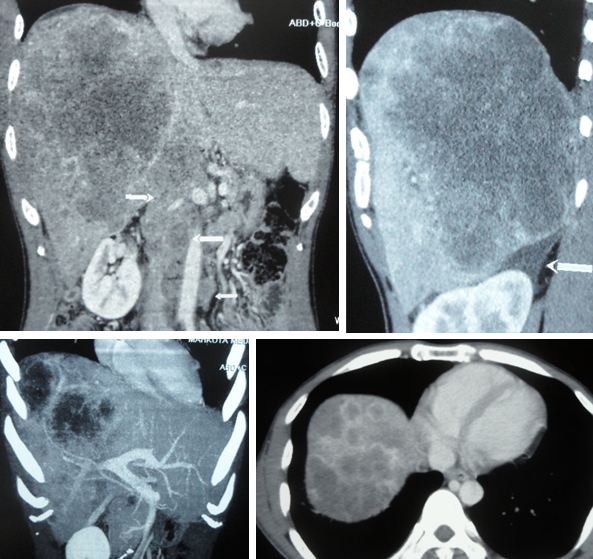

- Liver metastasis in both lobes, predominantly right lobe. The conglomerate of nodules in right lobe measures 11.4 x 15.1 x 18.1 cm. Mild ascites seen.

- Multiple para-aortic adenopathies, largest 1.8 x 2.2 cm.

Chest X-ray: Left lower zone nodules seen. Lung metastasis.